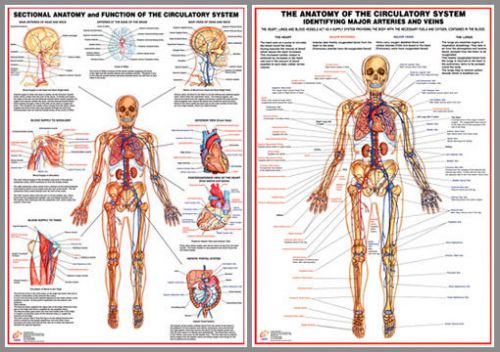

Anatomy of the CIRCULATORY SYSTEM Professional Fitness Wall Charts 2 Poster Set